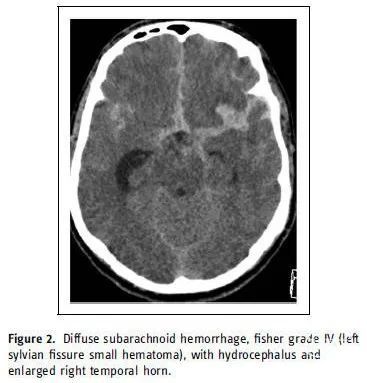

一名58岁的西班牙裔男性,既往无明显病史,因突发严重头痛和精神状态改变急诊来院。查体发现右侧偏瘫,对疼痛有反应。急诊非增强头部CT扫描显示弥漫性蛛网膜下腔出血(图2)。查体和影像符合Hunt-Hess 3级和Fisher IV级。头部CTA显示左大脑中动脉分叉部浅基底动脉瘤,具有复杂的不规则三叶结构。获得患者合法授权代表的知情同意后,立即将患者送往血管造影室使用SEAL™血管内治疗装置进行治疗。

图2. 弥漫性蛛网膜下腔出血,Fisher IV级(左外侧裂小血肿),伴脑积水和脑室右颞角扩大。